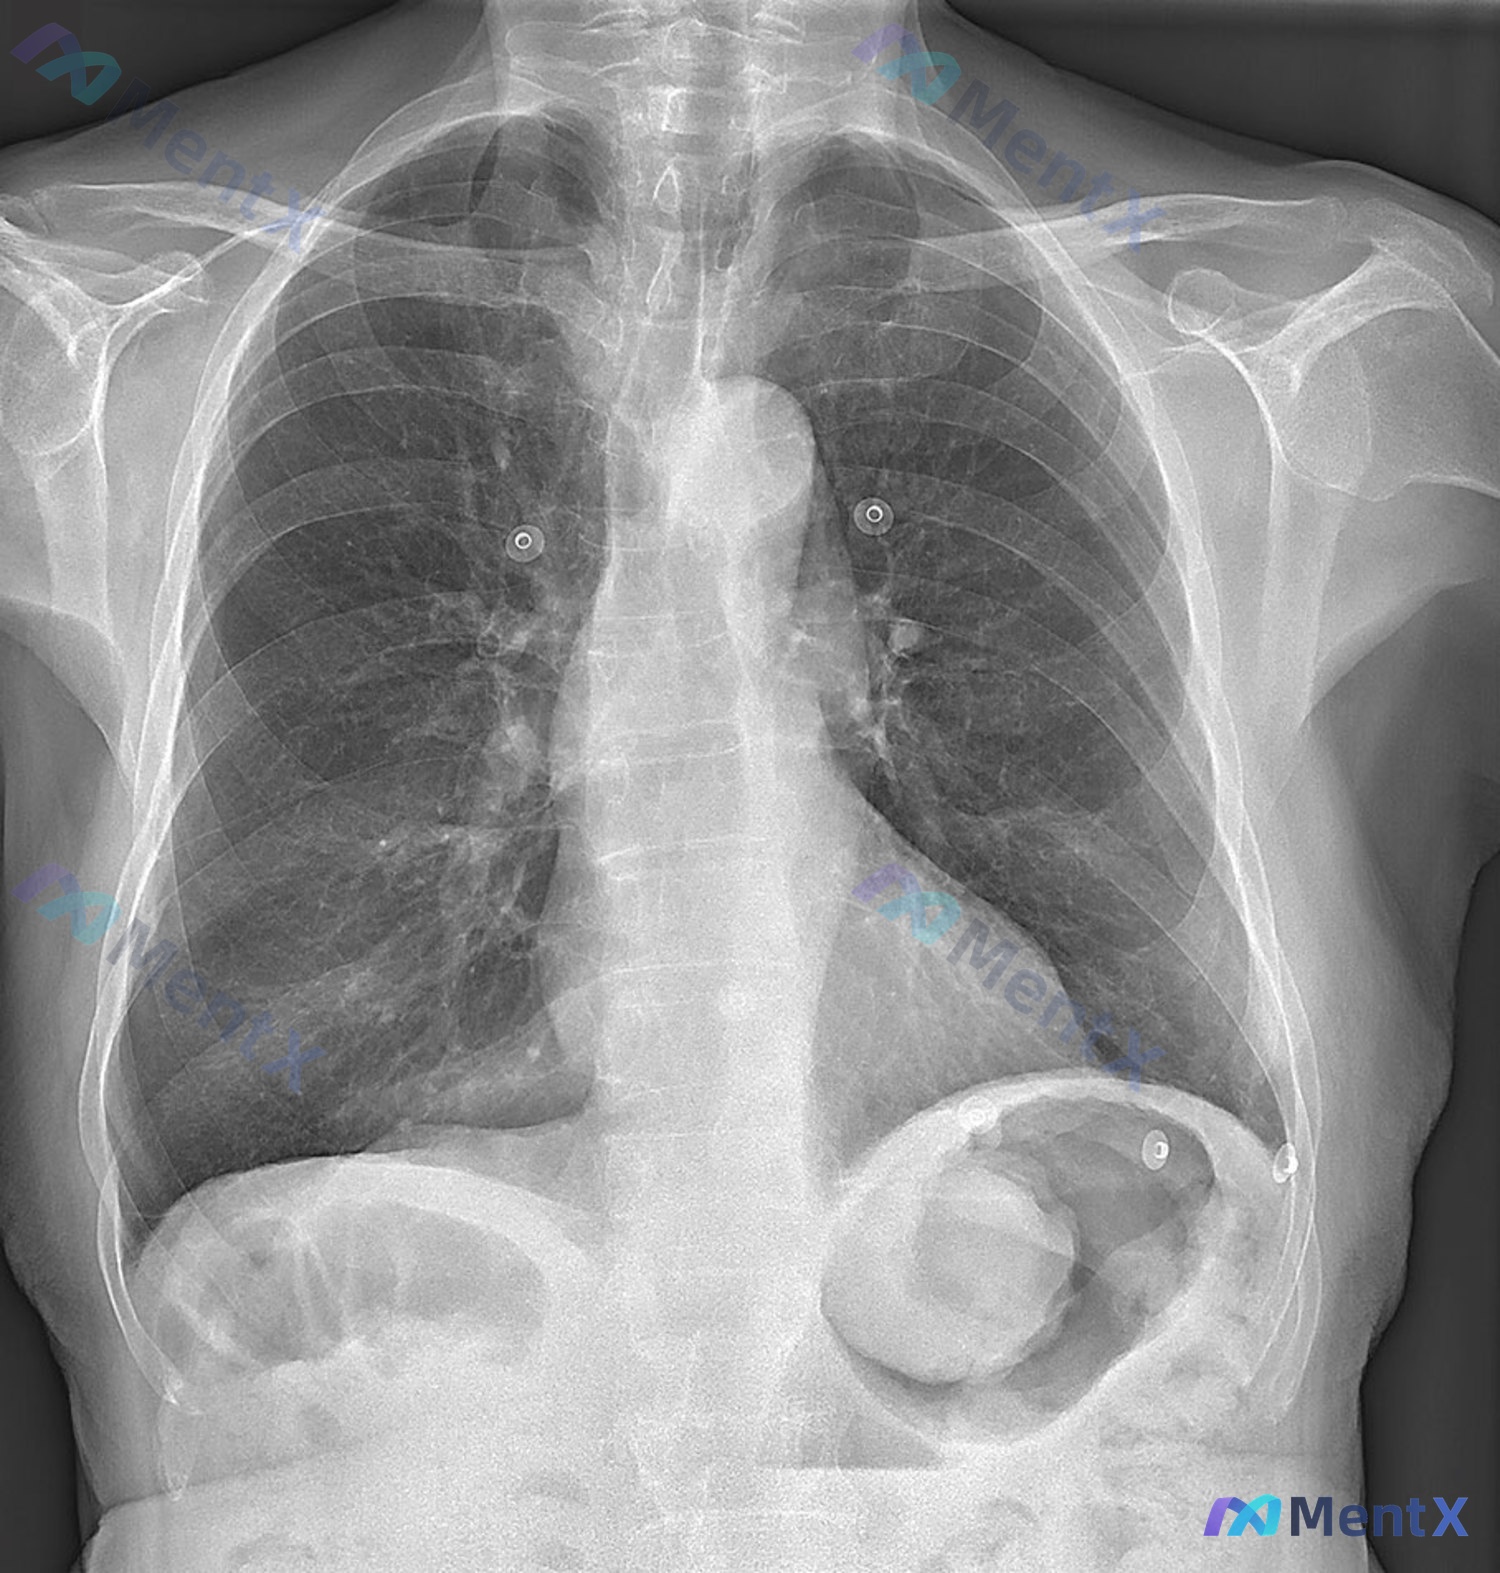

整理了一个有点「反直觉」的病例,核心是别被影像报告的「心肺正常」局限住思路。 病例基本信息 - 患者:90岁男性 - 主诉:双腿进行性水肿1个月,伴低血糖相关不适和头晕 - 病程:慢性进展性,1个月 关键影像信息(胸部正位片) 先看影像报告的描述: - 心影大小、心胸比正常,无肺淤血/实变/积液,双...